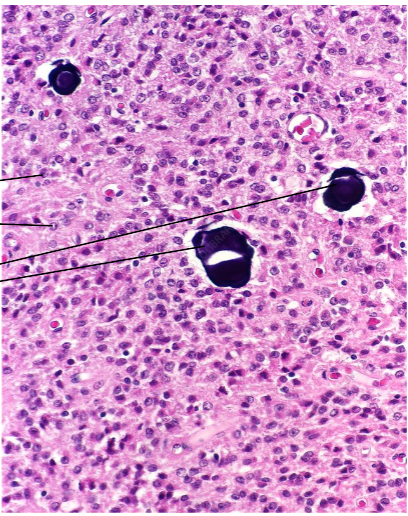

Identify the endocrine organ

Pineal Gland

What cells are these and what do they produce?

Pinealocytes, melatonin

What are the black structures

Calcified material